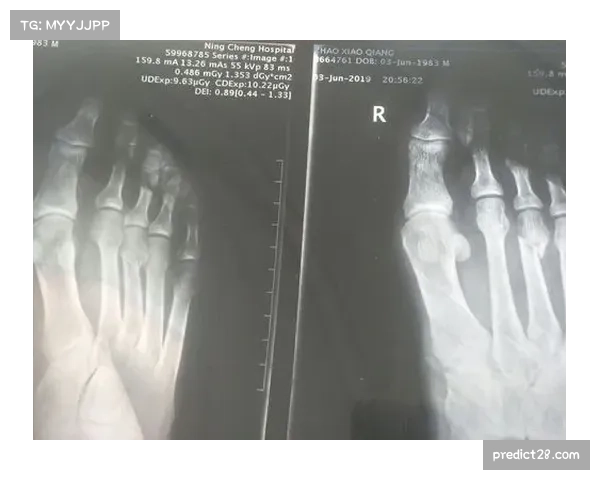

经过医生的紧急处理和初步检查后,雷迪克被送往医院进行了X光检查。检查结果显示,尽管雷迪克的手腕出现了明显的肿胀和疼痛,但幸运的是,并未出现骨折迹象。X光片清晰地显示手腕骨骼完好,骨折的风险可以排除。这一结果让雷迪克以及球队的工作人员松了一口气。

X光检查结果不仅证明了骨骼没有受到致命损伤,也使得球队能够迅速制定接下来的治疗和恢复计划。虽然没有骨折,但软组织损伤的可能性依然存在,这意味着雷迪克的手腕可能会经历一段较长时间的恢复期。医生建议他在短期内避免剧烈运动,并进行物理治疗,以减少肿胀并加速恢复过程。